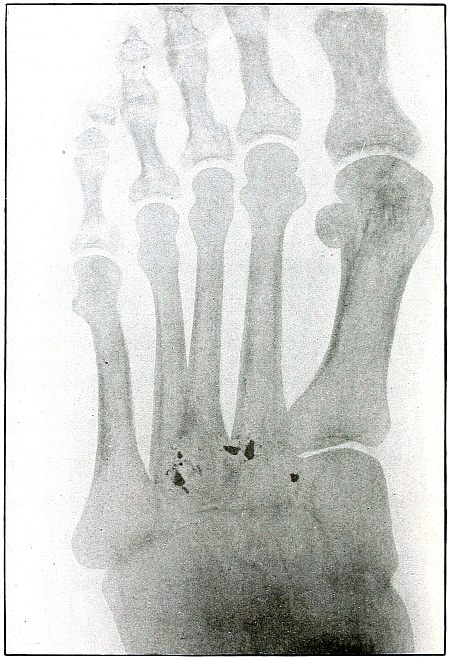

| 154. |

Gunshot wound, foot |

318 |

| 155. |

Gunshot wound, foot |

320 |

| 156. |

Gunshot wound, foot, multiple |

322 |